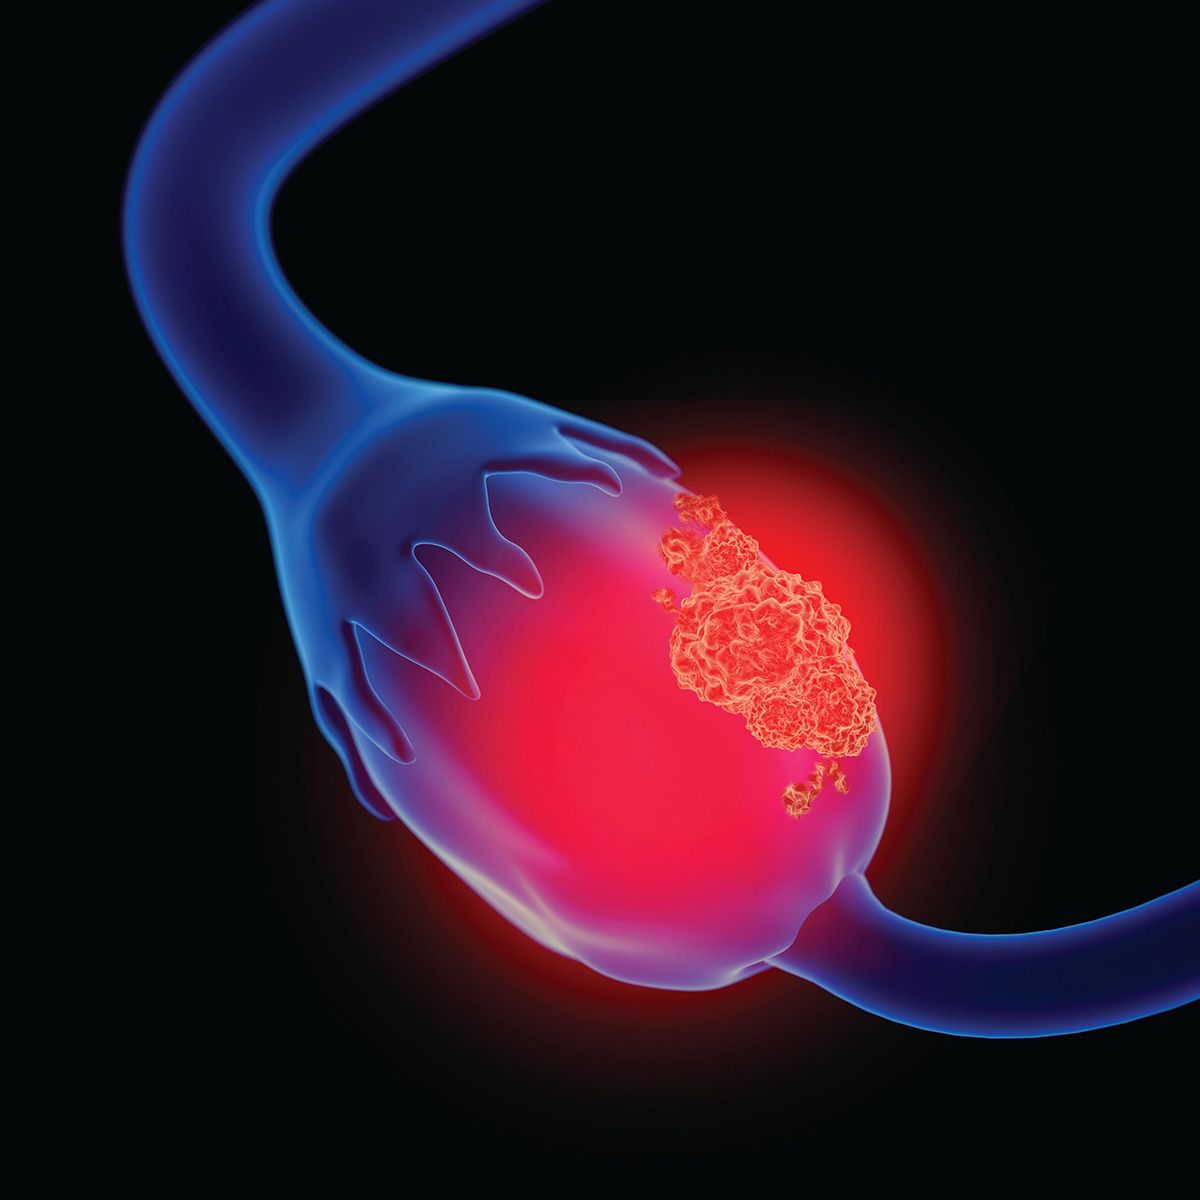

First Patient Dosed With Azenosertib in Cyclin E1+ Ovarian Cancer

The first patient with Cyclin E1-positive platinum-resistant ovarian cancer has been dosed with azenosertib in part 2a of the phase 2 registration-intent, DENALI clinical trial, according to a news release from Zentalis Pharmaceuticals, Inc. The …